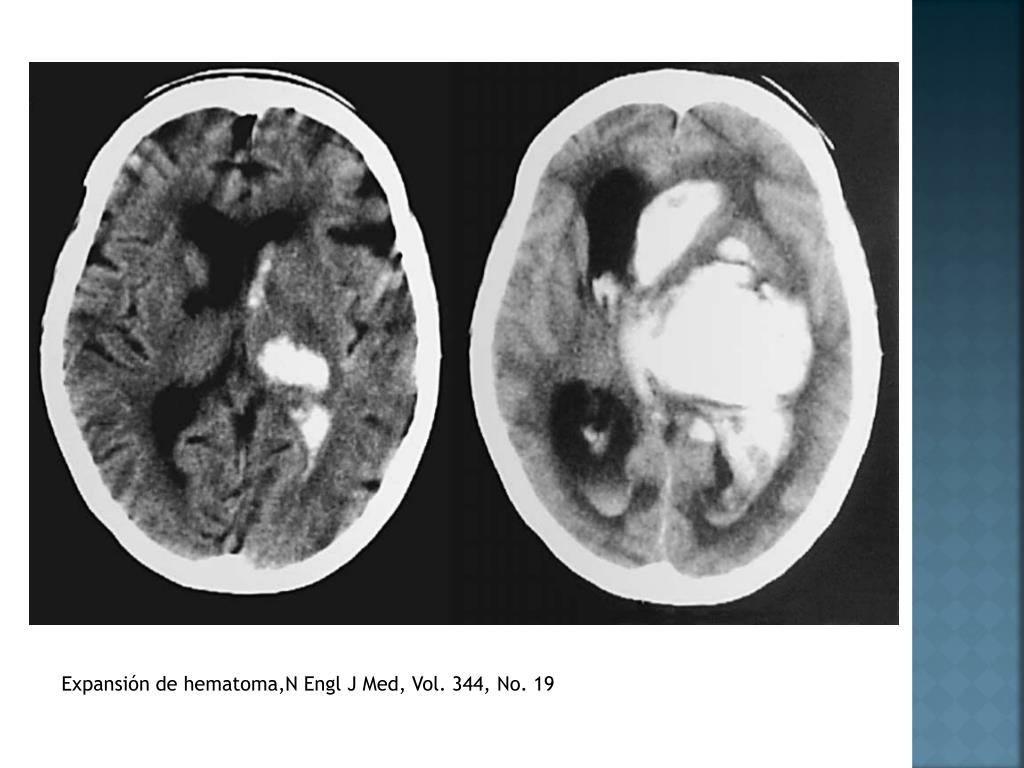

16. Expansión de hematoma,NEngl J Med, Vol. 344, No. 19

10. Lobar Ganglios basales 50% Tálamo Puente Cerebelo N Engl J Med, Vol. 344, No. 19, May 10, 2001

18. Tomografía axial computarizada (TAC) método dx. de elección (Clase 1A) • CT Angiography o TAC resalte de contraste • Expansión de hematoma (Clase IIB) • RMN (Clase 1A) • Hemorragia hiperaguda menor a 6 horas • Causa subyacente • Angiografía • Ptes. menores de 45 a • No riesgo de HIC primaria o hipertensiva • HSA • Estructuras vasculares prominentes • Hemorragia perisilviana o interhemisferica Management of intracerebralhemorrhage, Vascular Health and Risk Management 2007, Guidelinesforthe Management of SpontaneousIntracerebralHemorrhage, AHA/ASA 2010